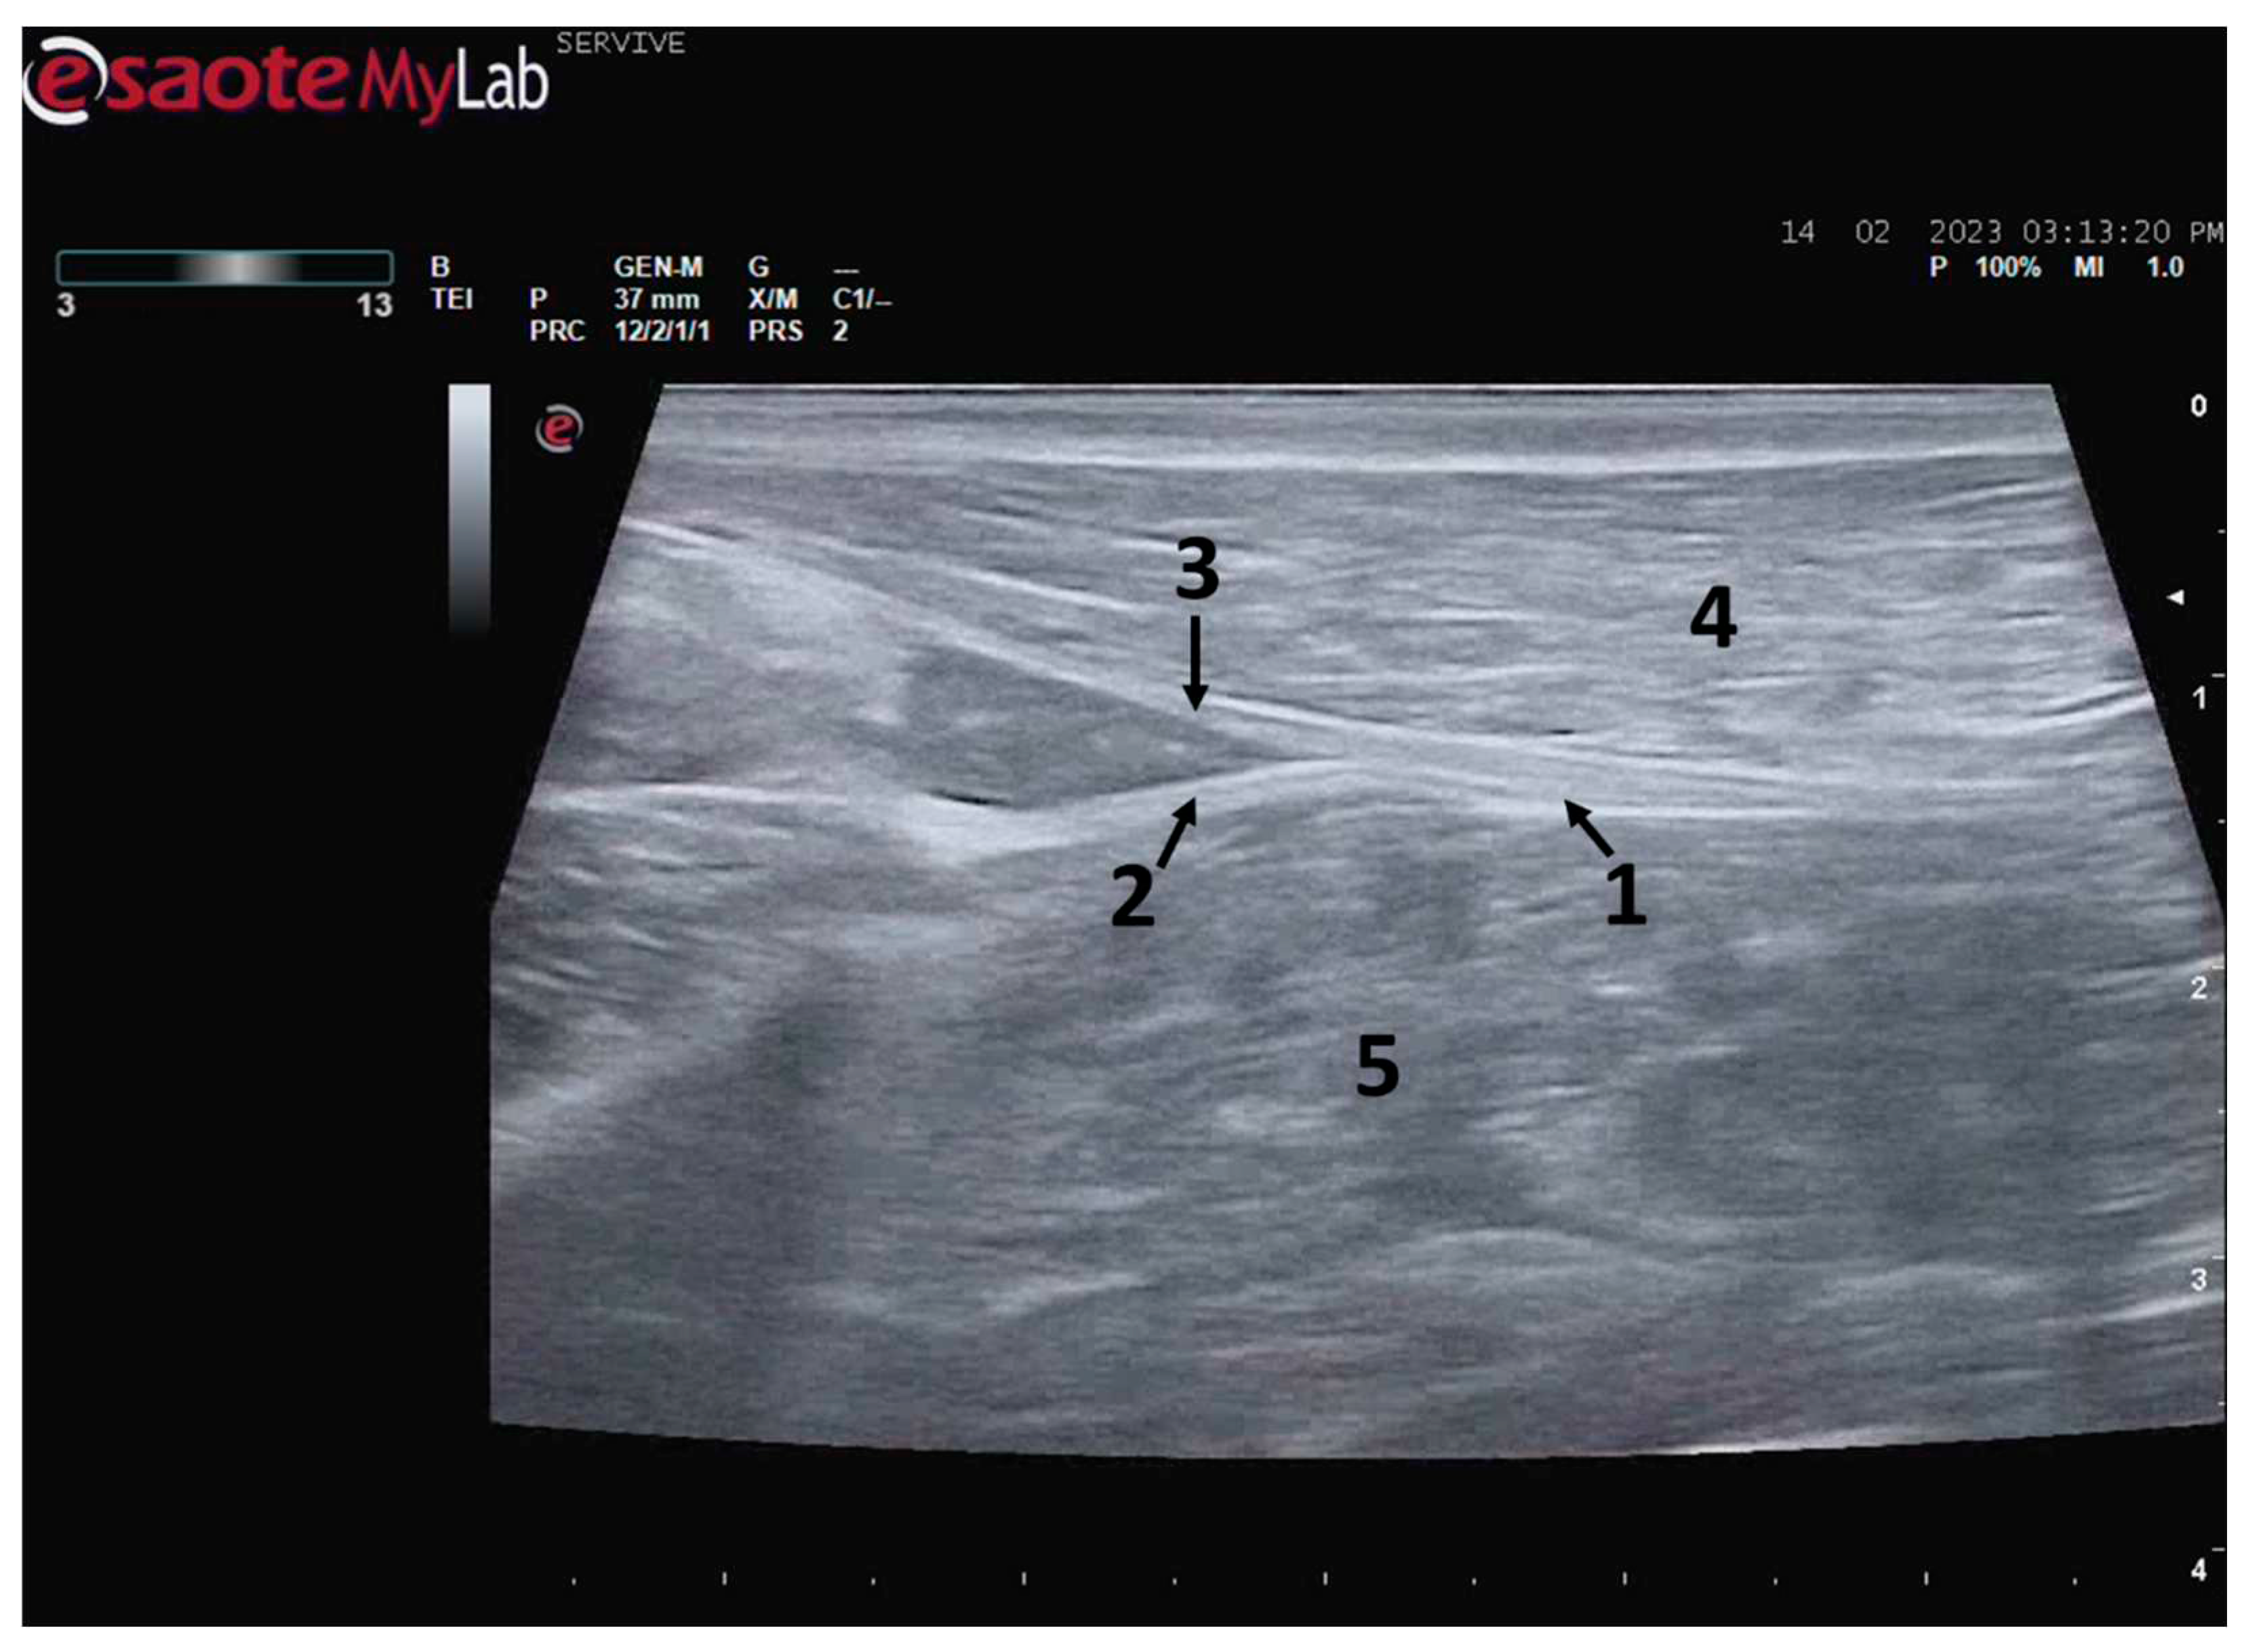

Figure 4.

Ultrasound image of the left sciatic nerve of a sheep nerve halfway through the thigh: 1) sciatic nerve (nerve fascicles enclosed by perineurium); 2) Epineurium; 3) biceps femoris muscle; 4) Piriformis muscle; 5) Adductor muscles. DIST1 represents the measurement of the diameter of the sciatic nerve halfway through the thigh.

The sciatic nerve was easily identified mid-thigh medially to the

biceps femoris muscle and caudal to the femur and

vastus lateralis muscle, allowing these muscles to be used as reference points for quick identification even for less experienced ultrasonographers. Monitoring the nerve in a proximal direction makes it possible to identify its passage between the greater trochanter of the femur and the ischial tuberosity, and these bony projections can be used as a reference point for its location. More proximally is its emergence from the greater sciatic foramen. At this level, the nerve may be more difficult to identify due to its curvature and also due to its proximity to the caudal gluteal artery and vein, but the use of a color-flow Doppler may clear up any doubts. A confusion with the sacred loin trunk in this region will be more unlikely since it is at greater depth. The sciatic nerve can also be easily tracked distally, to the point where it branches proximally to the stifle. As the nerve progresses, an increase in echogenicity seems to be observed, a phenomenon described in other species [

16], and which is probably related to an increase in the connective tissue within the nerve. It is important to remember that this increase in the amount of connective tissue is also related to an increased likelihood of compression or stretching injuries, makes it harder to observe the nerve and apply local anesthetic blocks [

26]. The mean diameter of the sciatic nerve measured mid-thigh and just before its branching site is identical to that indicated in other species, such as dogs of similar size. Its echographic appearance is similar to that described in other species such as humans [

27], dog [

14,

15] or cat [

16], appearing as a hypoechogenic tubular structure covered by a hyperechogenic envelope corresponding to the

epineurium, an aspect that allows its easy differentiation from soft tissues and bones in the vicinity. Before its branching site, the sciatic nerve diameter was also measured in a cross-section, rotating the probe 45 degrees from the position that allows obtaining the longitudinal image (